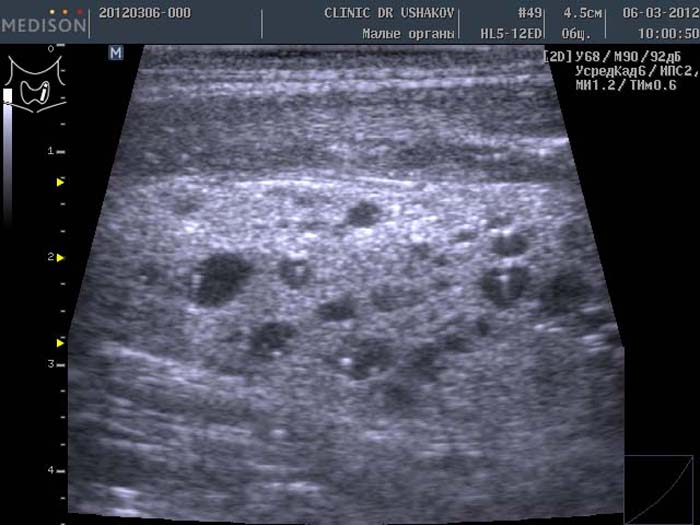

Очаговые образования в щитовидной железе представляют собой проблему эндокринологии. Это структурные изменения, которые не являются опухолевыми. Их называют узлами или кистами. Они обособлены от остального содержимого и имеют четкие границы, что видно на УЗИ.

По результатам эхогенного обследования новообразования делятся на следующие виды в зависимости от особенностей тканей и способности проводить ультразвуковую волну:

Гипоэхогенные образования выглядят как темные пятна с четкими или нечеткими границами. Они могут быть как злокачественными, так и доброкачественными, поэтому обязательным является биохимическое обследование.

Изоэхогенные образования щитовидной железы имеют нормальную плотность и практически не отличаются по структуре от окружающих тканей. Они характеризуются усиленным кровообращением по краям и твердым видимым ободком. Обычно считаются доброкачественными, за исключением редких случаев, когда диагностируется папиллярный рак.

Гиперэхогенные образования имеют эхогенность выше, чем окружающие ткани, и выглядят светлее. Они возникают в результате разрастания железистых тканей или отложения солей.

Анэхогенные структуры щитовидной железы практически не отражают ультразвук и выглядят как черные пятна. Они появляются при развитии кистозных форм или аденомы.